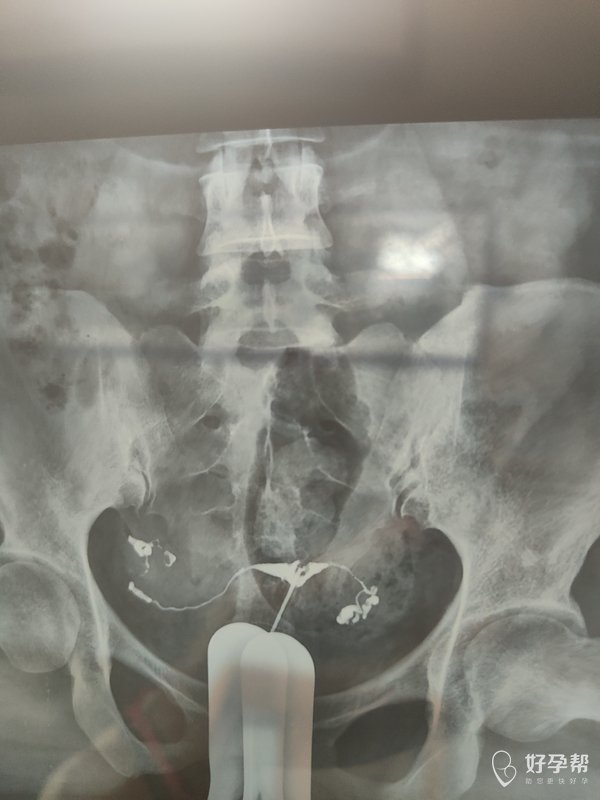

各位医生好前天做了输卵管造影请帮忙看看这些造

双侧输卵管通畅,弥散好,正常造影,可以试孕。